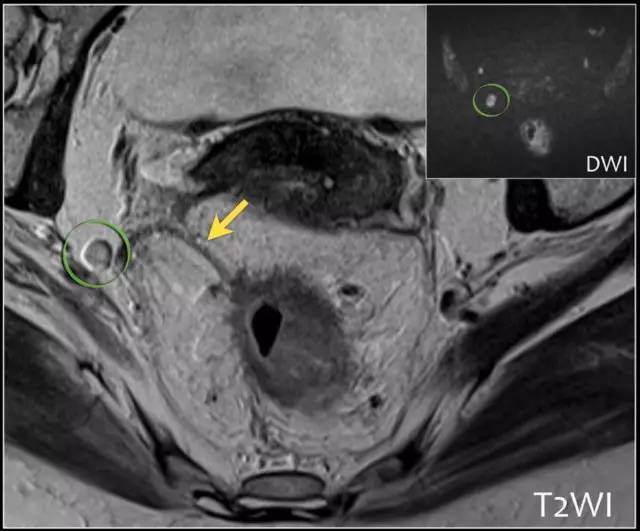

图 31 轴向 T2 加权图像报告 CRM 的距离。T3d 肿瘤局限于固有肌层内,肿瘤毗邻直肠系膜筋膜(箭头;肿瘤为 T2)。侵犯边界似乎是左后方(白色箭头),肿瘤的 CRM 评估为 5 mm。但有两个混合信号强度淋巴结(黑色箭头)邻接直肠,导致 CRM 为 0 mm。